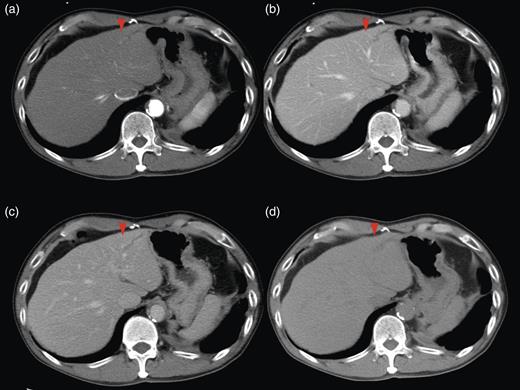

Magnetic resonance imaging (MRI) of the lateral segment lesion showed an irregular line shape lesion: hyper-intensity in T2-weighted; hypo-isointense in T1-weighted image (Fig. 2). These CT and MRI findings supported the identification of a fulfilment of tumour in B3. Endoscopic retrograde cholangiopancretography (ERCP) demonstrated a stricture involving the B2 and B3 hepatic ducts but not involving the left hepatic duct. Considering the patient's medical history along with the clinical features, the final diagnosis was secondary liver metastases due to primary descending colon adenocarcinoma, with the possibility of peripheral cholangiocarcinoma.